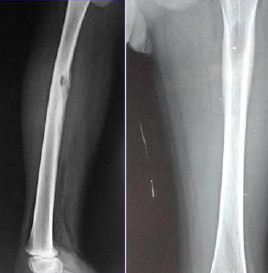

Bothaard langerhanscellen

bothaarden

X-foto: Patnaik S. et al. Imaging of Osseous Lesions in Langerhans Cell Histiocytosis (LCH). Indian J Appl Radiol 2017;3(1):114 (Creative Commons License 3.0 - Open Access Journal).